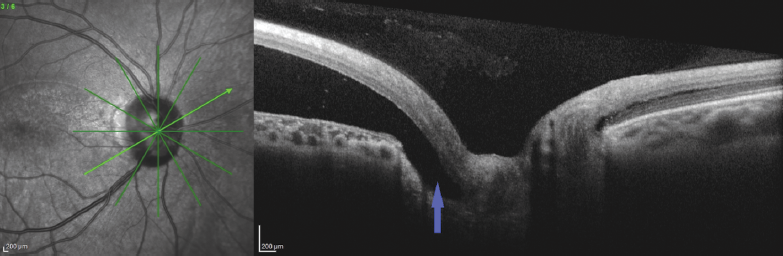

As per the FA data, in the area corresponding to the hyperfluorescence site, an RNFL defect was detected at the bottom of the excavation (Fig. 7).

Fig. 7. OCT of patient B. Vertical scan across the optic disc cup center (arrow – area of the retinal nerve fiber layer defect at the cup bottom)

Рис. 7. ОКТ пациентки Б. Вертикальный срез через центр экскавации диска зрительного нерва (стрелка — зона дефекта слоя нервных волокон сетчатки на дне экскавации)